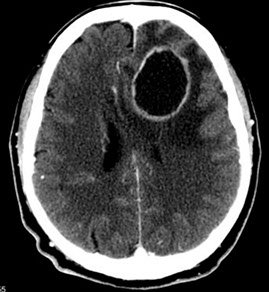

Huntington disease

AD trinucleotide repeat dz on cr 4p IT15 (HTT) gene c CAG repeats (***Caudate, ACh, GABA***)

- see atrophy of striatum (caudate nucleus and putament) ad frontal cortex

-- bc caudate borders lateral ventral ventricles, caudate atrophy causes hydrocephalus ex vacuo

Gross: atrophy of the caudate nucleus and putamen associated with a diffuse neuronal loss.

Sx Chorea, depression, progressive dementia

Dx: Atrophy of caudate nucleus and >40 CAG repeats